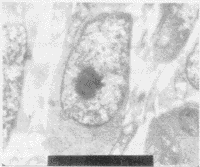

免疫组化结果显示,HCY-2蛋白在转基因胚胎脑细胞中呈强阳性表达,均定位于细胞质中;空载质粒对照组HCY-2蛋白阳性细胞基本不可见(图1和图2)。

图1 第3组,胚脑HCY-2蛋白表达阴性,ABC法×100

图2 第4组,胚后脑部HCY-2蛋白表达阳性,ABC法×100

空载质粒对照组胚脑细胞超微结构正常,未观察到凋亡细胞。转基因组可见脑细胞间缝隙连接减少,细胞形态变异,电子密度增高;溶酶体和空泡增多,线粒体肿胀或固缩,内质网和高尔基体亦有不同程度肿胀,核糖体不丰富;细胞核形态不规则,出现切迹;核内异染色质增多,浓缩成团块状和边缘化,核仁分裂。观察到凋亡细胞(图5和图6)。

图5 第3组,正常脑细胞,透射电镜,×10000

图6 第4组,胚脑细胞凋亡,透射电镜,×10000